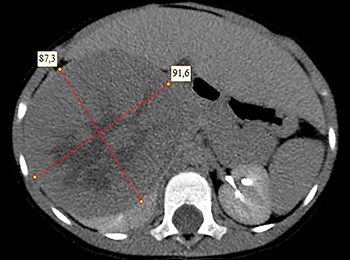

Рисунок 1. КТ брюшной полости ребенка с большой нефробластомой с метастазами в печень.

Клинически: при пальпации опухоль в проекции правой почки до 12 см в диаметре. Общеклинические исследования в пределах возрастной нормы. При КТ органов брюшной и грудной полости: КТ-картина объемного образования правой почки без признаков интрапульмональных метастазов (см. рис. 2). УЗИ брюшной полости: в проекции правой почки солидно-кистозное образование 101ґ114ґ99 мм, объемом 500 мл, васкуляризация активная, интактная часть почки 57ґ12ґ40 мм. Объемное образование правой почки — опухоль Вильмса. Предварительный диагноз: опухоль Вильмса правой почки, 2-я стадия.

Ребенку проведена предоперационная химиотерапия. На 5-й неделе лечения КТ-контроль показал уменьшение опухоли в размерах до 90ґ80ґ100 мм (см. рис. 3).